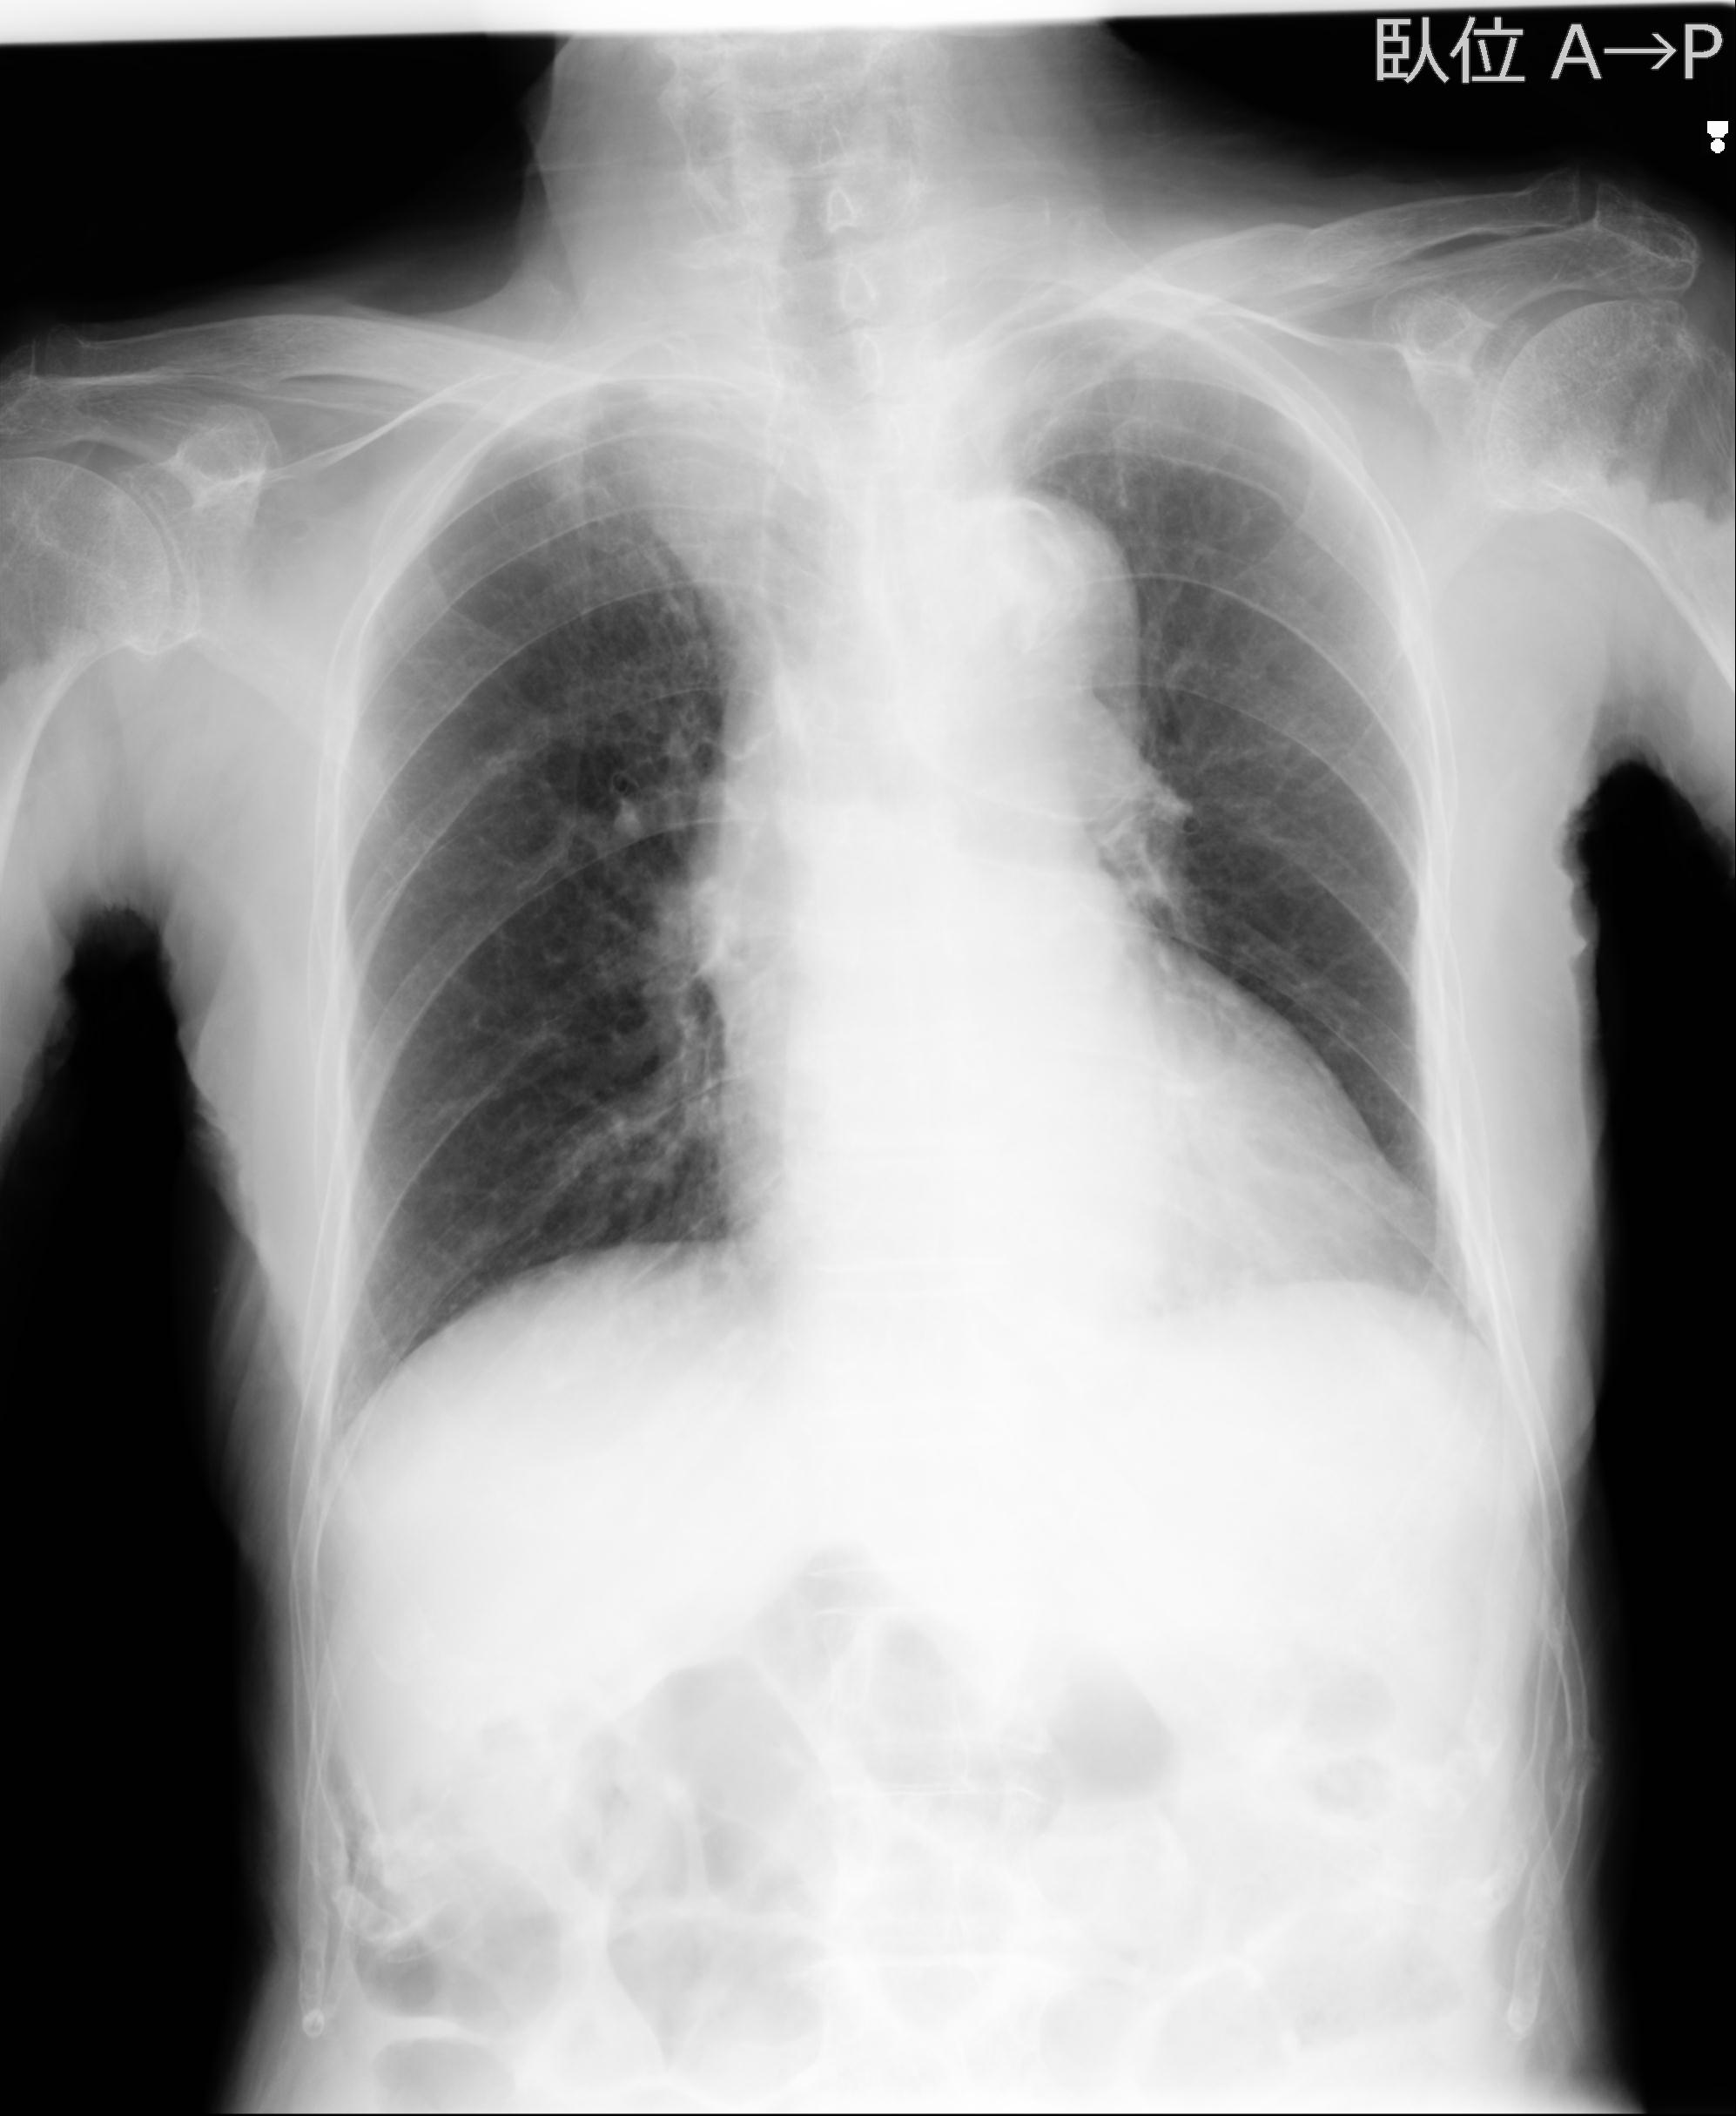

症例写真集